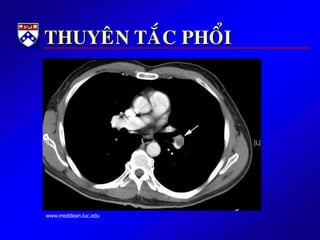

THUYEÂN TAÉC PHOÅI

 HUYEÁT KHOÁI TRONG LOØNG

TM GAÂY TAÉC ÑM PHOÅI

 HK THÖÔØNG ÔÛ CHI DÖÔÙI

HOAËC KHUNG CHAÄU

 GAÀN ½ BN TTP KHOÂNG ÑÖÔÏC

CHAÅN ÑOAÙN

 TÖÛ VONG 30% NEÁU KHOÂNG

ÑIEÀU TRÒ.

 TÆ LEÄ TÖÛ VONG GIAÛM COØN 2-

8% NEÁU ÑIEÀU TRÒKÒP THÔØI

 Beänh söû: ÑN kieåu maøng phoåi, khôûi phaùt ñoät ngoät, khoù

thôû, quaù trình naèm laâu, coù tieàn caên huyeát khoái chi döôùi,

or ñau /söng chaân

 Khaùm: ral rít ôû phoåi, nhòp tim nhanh, huyeát aùp thaáp,

SpO2 thöôøng bình thöôøng, phuø chaân thöôøng 1 beân

 Xeùt nghieäm: D-dimer, V/Q scan, CT scan ngöïc

 Ñieàu trò:khaùng ñoâng; xeùt chæ ñònh söû duïng tieâu sôïi huyeát

or phaãu thuaät laáy huyeát khoái neáu thuyeân taéc phoåi naëng.

www.meddean.luc.edu